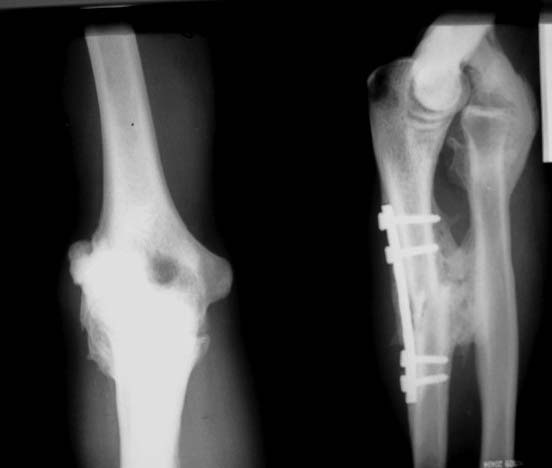

> Мужчина 27 лет, травма год назад - удар по предплечью электропоездом.В ЦРБ

> - остеосинтез

> локтевой кости, вероятно - открытое вправление вывиха головки лучевой

> кости (выписки нет,

> но пациент говорит, что были металлические спицы и есть п/операционный

> рубец в проекции

> головки лучевой кости). В настоящее время: движения в локтевом суставе

> отсутствуют.

> предплечье находится в положении сгибания 160*. Хочется услышать мнения об

> объеме

> оперативного вмешательства, во сколько этапов его проводить.